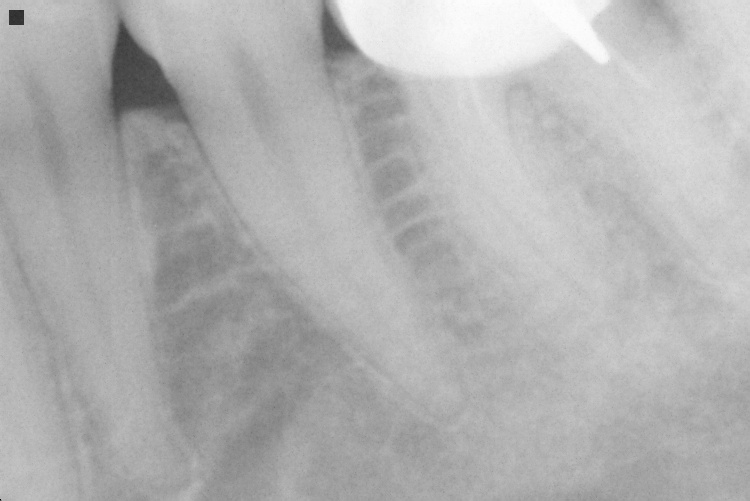

Name Last modified Size Description Parent Directory - IO000001.jpg 2020-07-28 13:55 84K IO000002.jpg 2020-07-28 13:55 68K IO000003.jpg 2020-07-28 13:55 83K IO000004.jpg 2020-07-28 13:55 92K